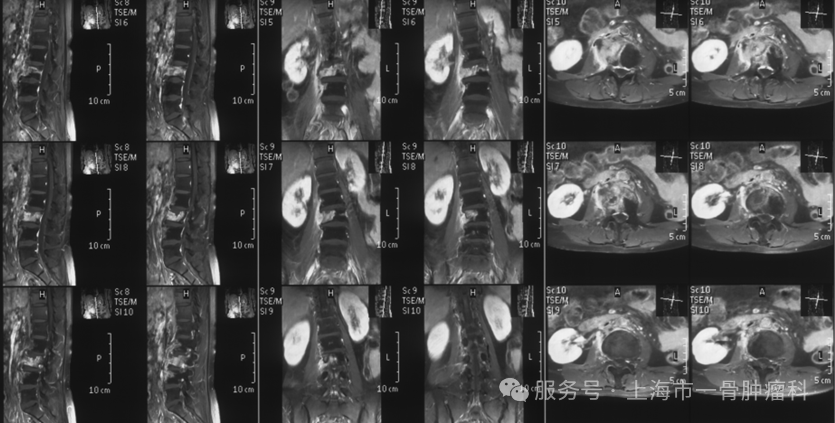

图1:术前腰椎MRI提示L3椎体异常信号,右侧椎体侧方腰大肌受累,累积多节段,脊髓未见明显受压